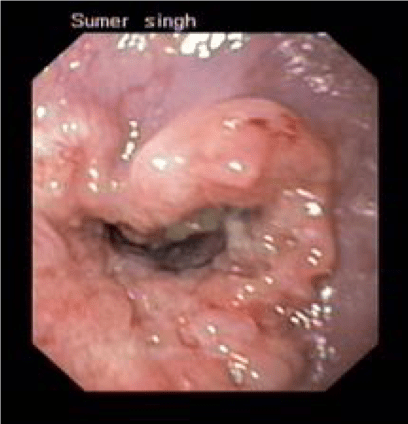

- Banding of varices